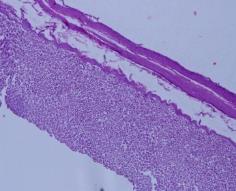

Microscopic examination of stomach:

Sections show a wall of gastric mucosa with intact architecture. The gastric mucosa is thrown into gastric pits and folds revealing well organized glandular structures. The underlying submucosa is scanty and in unremarkable. Well organized muscular layer is seen beneath, lined externally by serosa. No significant pathology is seen in any of the sections examined.

Fig. 1: Microscopic examination of male rabbit’s heart, stomach, liver and kidney tissues treated with S. nigra extract